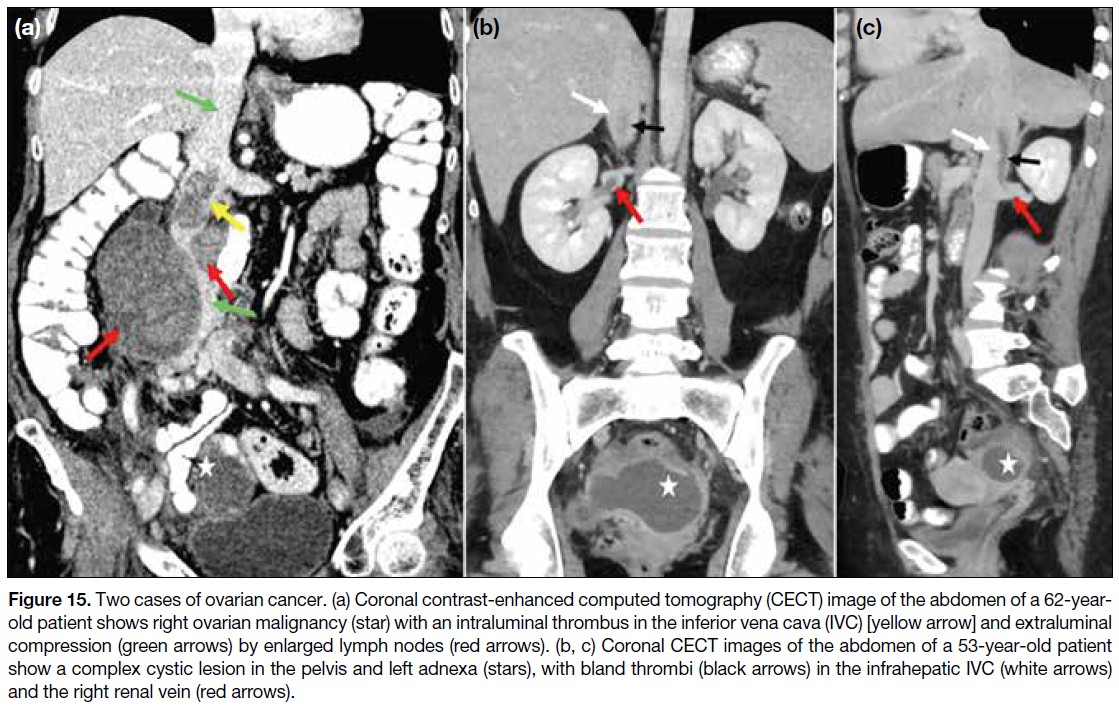

Cancer-associated thrombosis is recognised as the

most common complication of cancer and is attributed

to several factors (Table 2).[7] [8] [9] [10] [11] [12] Compared with the

general population, patients with cancer have a 12-fold increased risk of developing venous thrombosis, as well

as a significantly worse prognosis[9] [10] (Figure 14). The

IVC and its tributaries, especially the renal and gonadal

veins, should be assessed in all abdominal malignancies to exclude thrombosis (Figure 15). Postsurgical venous

thromboembolism is the leading cause of postoperative

death in cancer patients, and IVC thrombosis is associated

with substantial morbidity and mortality.[11] [12]

Figure 15. Two cases of ovarian cancer. (a) Coronal contrast-enhanced computed tomography (CECT) image of the abdomen of a 62-year-old

patient shows right ovarian malignancy (star) with an intraluminal thrombus in the inferior vena cava (IVC) [yellow arrow] and extraluminal

compression (green arrows) by enlarged lymph nodes (red arrows). (b, c) Coronal CECT images of the abdomen of a 53-year-old patient

show a complex cystic lesion in the pelvis and left adnexa (stars), with bland thrombi (black arrows) in the infrahepatic IVC (white arrows)

and the right renal vein (red arrows).